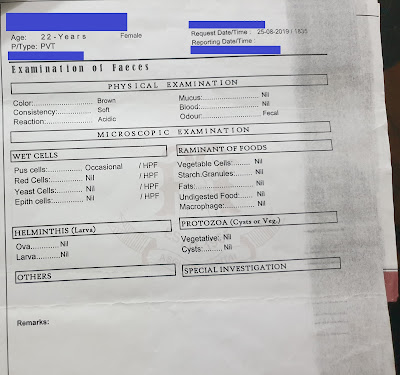

- In August 2019, she got admitted again in the hospital for 3 days by GP. Multiple tests were done and nothing was found. Last day of discharge she got fever so GP delayed the discharge by one more day.